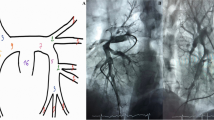

Mechanical thrombectomy was achieved using the FlowTriever System via large-bore transfemoral venous access. Full details of the procedure have been reported previously [11]. In brief, the Triever Catheter (16, 20, or 24 Fr) was advanced over an 0.035” guidewire into the pulmonary arteries for thrombus aspiration. If needed, the FlowTriever Catheter was advanced through the Triever Catheter over the guidewire for mechanical thrombus dislodgment and removal. Pulmonary angiography and right heart catheterization were performed immediately before and after the thrombectomy. A suture-based closure device was used. Procedure time was defined as the time from gaining venous access until sheath removal.

Table 3 summarizes the invasive and non-invasive hemodynamic data. Before thrombectomy, mean sPAP (51.3 ± 11.6 mmHg) and mPAP (29.8 ± 9.1 mmHg) were severely elevated. On table, mean sPAP, diastolic PAP (dPAP), and mPAP dropped by -15.0 mmHg (95%: -18.9 to -11.0; p < 0.001) (Fig. 1), -3.8 mmHg (95% CI: -6.6 to -1.1; p = 0.008), and − 8.4 mmHg (95% CI: -11.0 to -5.8; p < 0.001), respectively. While 2 (7%) patients had an sPAP > 70 mmHg before thrombectomy, none of the patients had an sPAP > 70 mmHg post-thrombectomy.

From post-thrombectomy to three months, mean sPAP (p = 0.002) continued to decrease (Table 3). Compared with before thrombectomy, sPAP (-23.2 mmHg, 95% CI: -28.5 to -17.8; p < 0.001), dPAP (-6.7 mmHg, 95% CI: -11.6 to -1.8; p = 0.010), and mPAP (-12.0 mmHg, 95% CI: -16.8 to -7.2; p < 0.001) were significantly lower at three months. The change in sPAP from pre-thrombectomy to post-thrombectomy (r=-0.76; p < 0.001) and three months (r=-0.80; p < 0.001) strongly correlated with the pre-thrombectomy sPAP (Fig. 2). The proportion of patients with mPAP ≤ 20 mmHg increased on table and continued to increase until three months (Cochran’s Q p = 0.001) (Fig. 3).